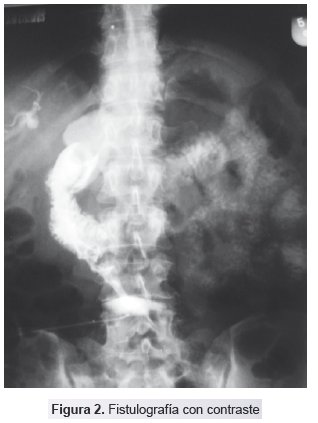

Fistulografía: Reporta fístula colecisto entero-cutánea, colelitiasis y ¿síndrome de Mirizzi? (Fig. 2).